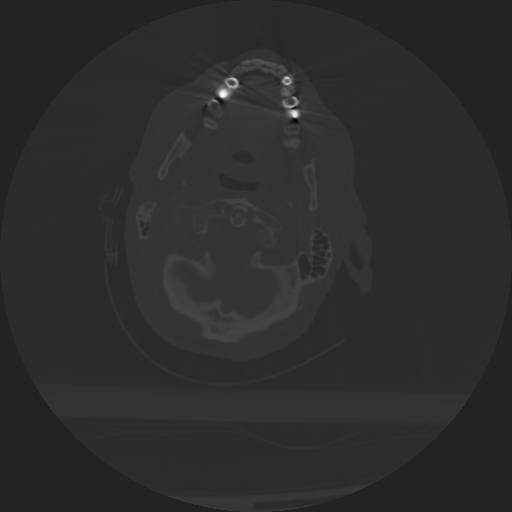

22 ANGIO,CE,Vol,0.5,ANGIO,,